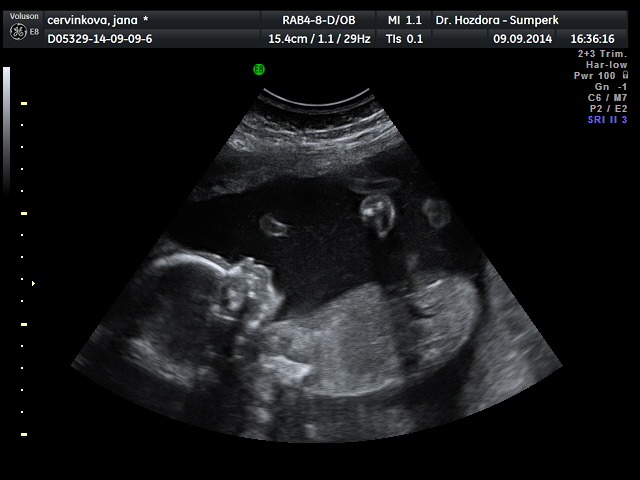

Děvčata,tak mám po velkém ultrazvuku a v lednu se nám narodí zdravá holčička jménem Marie Jana

Jani, úplně mě zalechtalo u srdíčka, ty fotky jsou nádherné. Já bych do 4D taky šla, je to sice dost peněz, ale je to na celý život